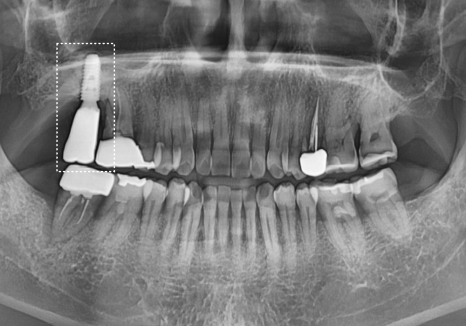

방사선 사진 결과, 잇몸뼈 소실이 너무 심해

주변 치아까지 위험할 수 있어

안타깝지만 빠른 발치를 결정했습니다.

다만, 오랜 염증으로

뼈 상태가 좋지 않아 바로 심기보다는

뼈가 깨끗하게 안정될 때까지 기다린 후

상악동 거상술을 진행하기로 했습니다.

발치 후 뼈가 안정화된 것을 확인한 뒤,

상악동 거상술을 통한 뼈이식과 함께

임플란트를 안전하게 식립했습니다.

사진으로 봐도 뼈가 아주 예쁘게 잘 이식되었죠?

그로부터 3개월 뒤,

임플란트와 뼈가 완전히 하나가 된 것을 확인하고

지르코니아 보철을 올려 마침내 치료를 끝냈습니다.